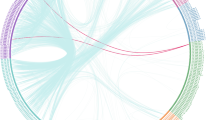

Compared with the HC group, the MDD group showed significant decreases in rs-FC between the thalamus and SI in two clusters. As shown in Fig. 1 and Table 2, both clusters were in the right central posterior gyrus: the first cluster had the maximally intense voxel at MNI coordinates x = 27, y = − 33, z = 75 (8 voxels, about 216 mm3, T = 3.6162, p < 0.05 AlphaSim correction), and the second cluster had the maximally intense voxel at MNI coordinates x = 45, y = − 30, z = 63 (8 voxels, about 216 mm3, T = 3.2803, p < 0.05 AlphaSim correction).

As shown in Fig. 2, significantly different brain regions and patient clinical symptoms in the SHAPS total score (r = − 0.383, p = 0.033), delayed memory score (r = − 0.376, p = 0.037), and two-digit continuous operation test score (r = − 0.369, p = 0.041) showed significant negative correlations. The significantly different brain regions had no significant correlation with the other scores.

In MDD patients, brain areas significantly different levels of connectivity were negatively correlated with cognitive function, including SHAPS total score (r = − 0.383, p = 0.033), delayed memory score (r = − 0.376, p = 0.037), and two-digit continuous operation test score (r = − 0.369, p = 0.041) as shown in (a, b, and c), respectively